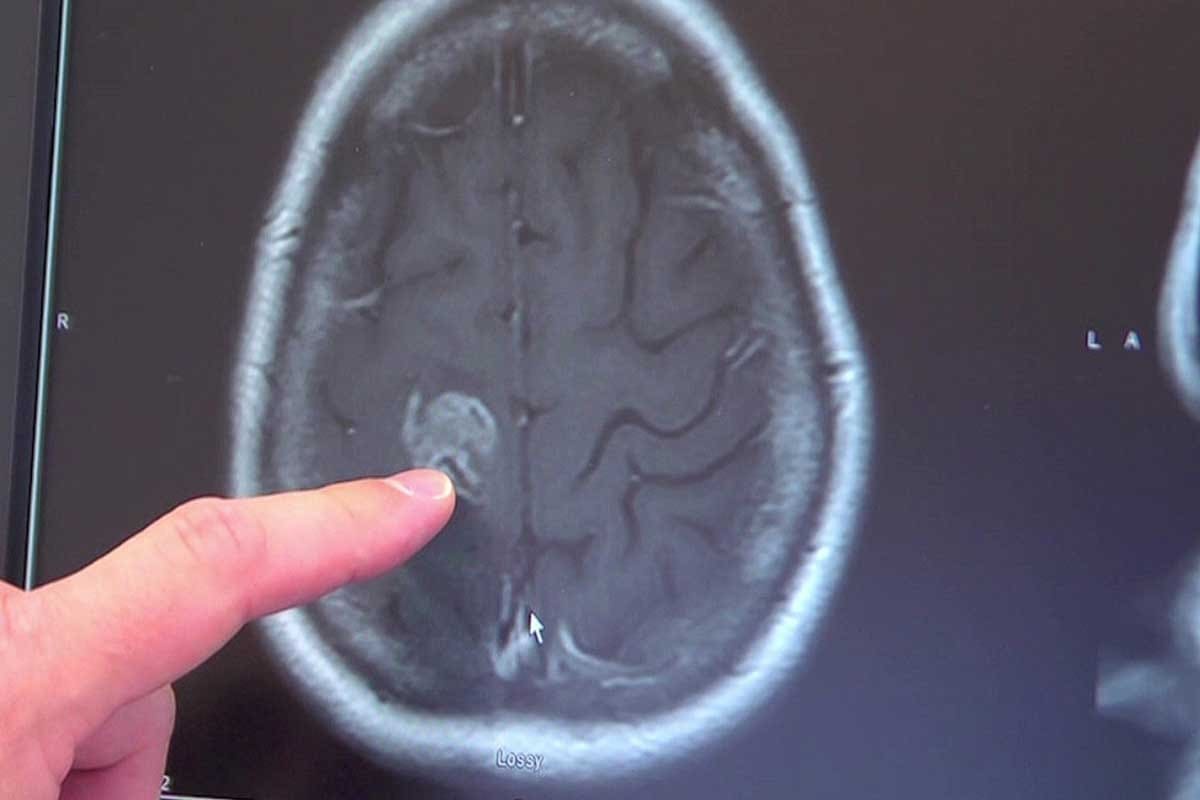

When a patient is referred to us with a suspected cancer diagnosis, we begin with a thorough initial assessment. This includes a detailed medical history, physical examination, and a review of any previous diagnostic tests. We use this information to guide further testing, which may include imaging studies such as CT scans, MRI, or PET scans, as well as laboratory tests like blood work and biopsies.

Imaging studies play a crucial role in diagnosing and staging cancer. For instance, a CT scan can help identify the size and location of tumors, while a PET scan can provide information on the metabolic activity of cancer cells. Laboratory tests, including biopsies, are essential for confirming the diagnosis and understanding the specific characteristics of the cancer.